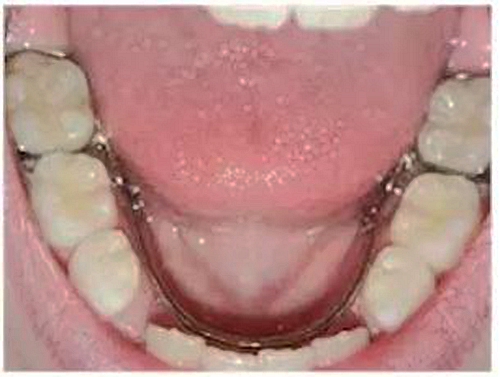

②舌弓式間隙保持器

乳牙缺失致恒牙“亂長(zhǎng)”,這個(gè)“間隙保持器”可預(yù)防

這種間隙保持器用于下牙左右兩側(cè)都有缺牙的情況,“舌側(cè)”是指牙齒靠近舌頭的那面。這種保持器的兩端固定在兩側(cè)缺失牙后方的牙齒上,一個(gè)弓絲沿著下牙的內(nèi)側(cè)連接兩段的帶環(huán)。